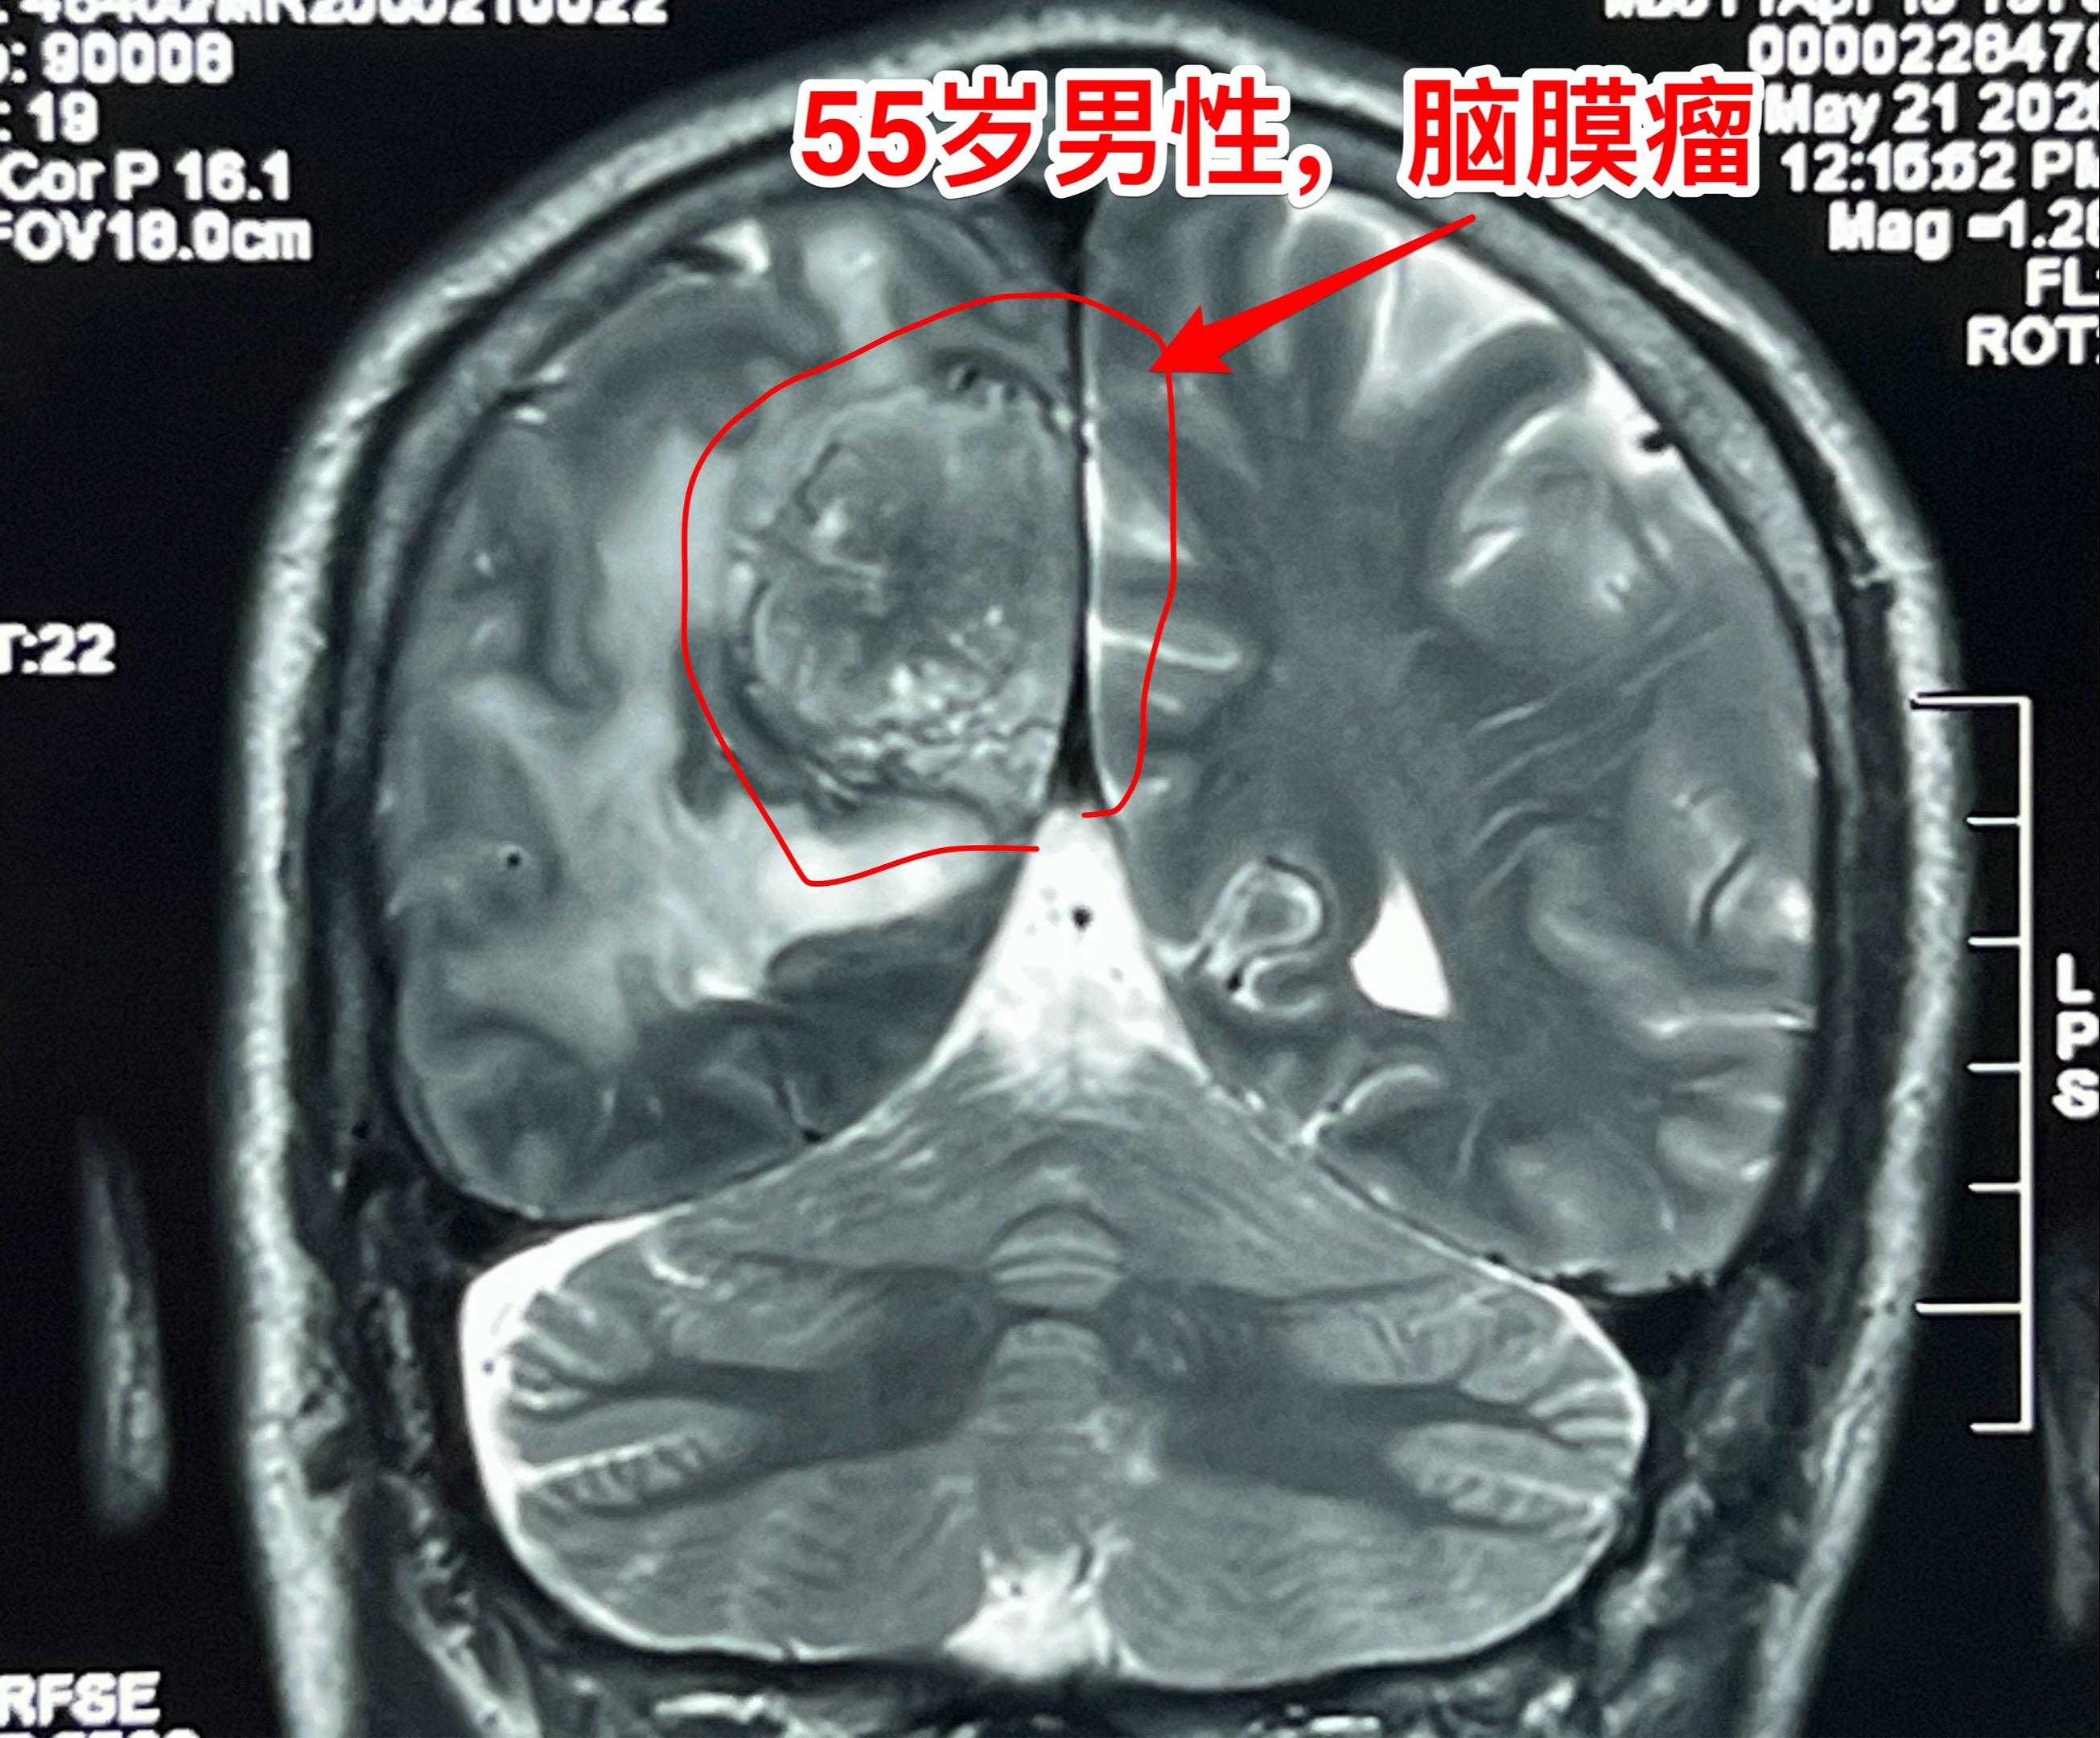

55岁男性因头痛发现脑膜瘤。脑膜瘤是良性肿瘤,如果有症状的话,就应该作手术切除肿瘤。彻底切除脑膜瘤是有希望获得治愈的。 这个脑膜瘤切除手术难度不算太大,今天加班作了手术,晚上就从ICU转回普通病房了。